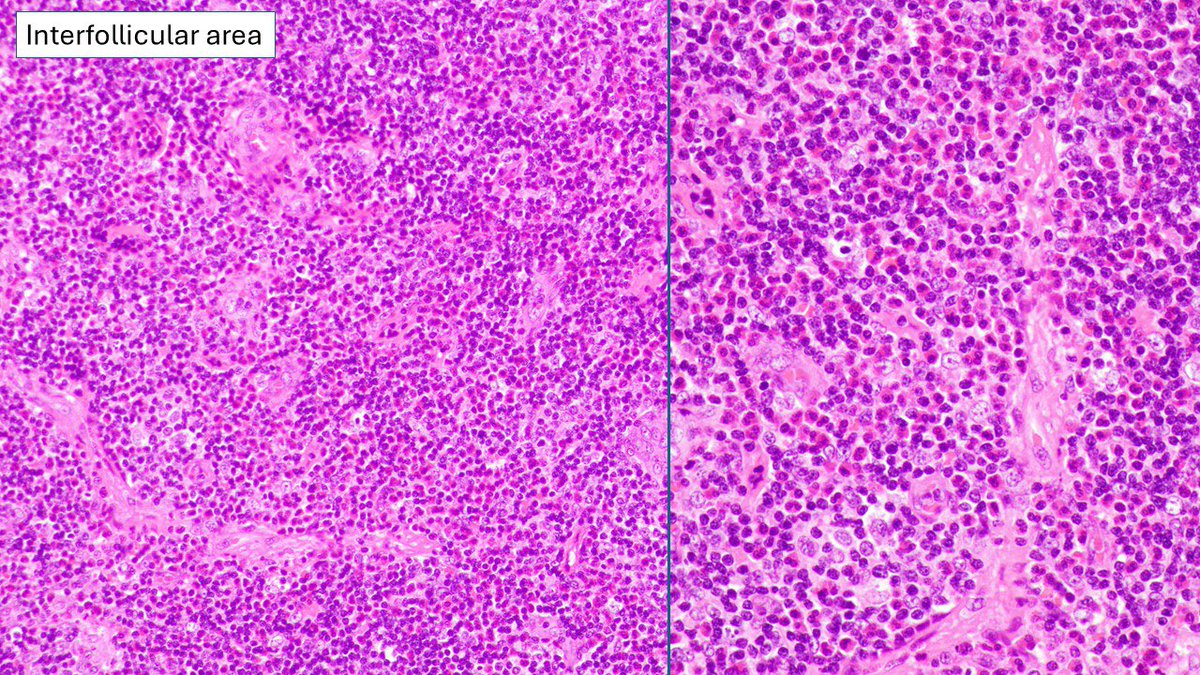

Pathologists! What do you make of this enlarged pre-articular lymph node in adult male originally from India? Otherwise, asymptomatic, no enlarged nodes away from head and neck. #HemePath #Lymphadenopathy #lymphnode

6

19

62